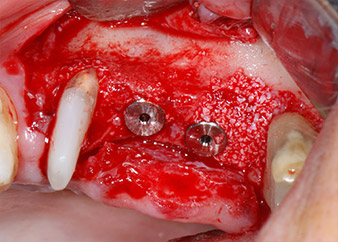

Les implants (Restore, Keystone Dental, 3,75 mm de diamètre, 8,0 mm de long) ont été mis en place à l'aide du moteur d'implantologie (Fig. 11 et 12).

Les défauts osseux autour des implants, sur la face mésiale de la dent 27 et autour de la racine de la dent 24, ont été reconstruits par des particules de substitut osseux xénogénique et recouverts d'une membrane collagène résorbable (Bio-Gide, Geistlich Biomaterials) pour une augmentation par GBR (Fig. 13 et 14).

Enfin, après incision du périoste, le site a été suturé avec repositionnement passif d'un lambeau d'avancement coronaire, à l'aide d'un matériau de suture résorbable 5-0 (Fig. 15). La radio postopératoire montre les deux implants dans leur position verticale correcte (Fig. 16).